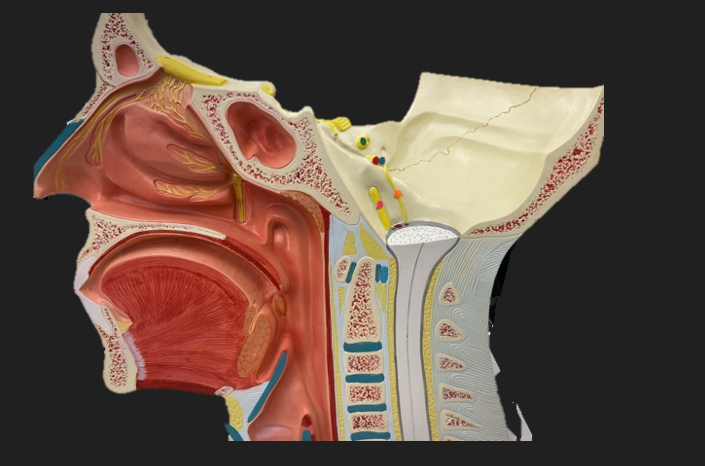

green dot

spinal nerve

orange dot

ventral root

pink dot

dorsal root

blue dot

dorsal root ganglion

red dot

dorsal ramus

yellow dot

ventral ramus

purple dot

anterior median fissure